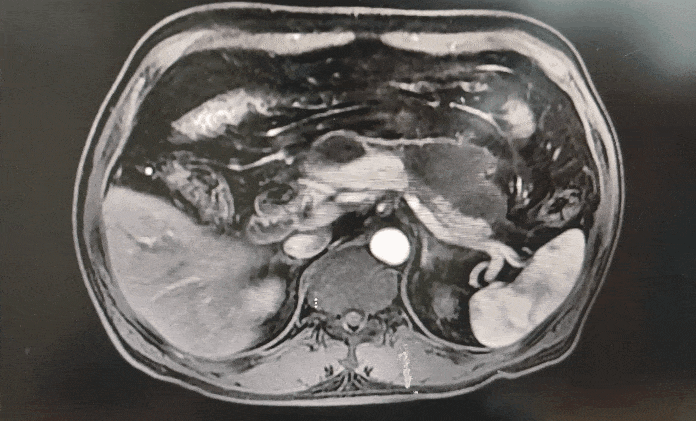

◈ 2022-11-28,TTFields联合化疗治疗2个月,上腹部MR增强扫描,对比基线( 2022-09-13):胰周多发囊性病变,考虑为术后改变(活检后),假性囊肿形成可能,较前略吸收;局部与邻近胃壁分界不清,左侧门脉高压,胃底、肠系膜静脉曲张,脾静脉近段较前显示清楚,肠系膜上动脉、腹腔干近段及局部分支周围软组织影较前范围缩小。

2022-11-28上腹部MR增强扫描—TTFields联合化疗治疗两个月